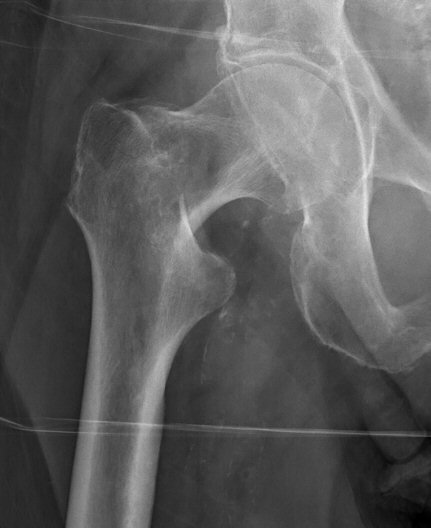

- Cervikal, fraktur av kollum femoris. Klassificeras enligt Garden som bedöms på frontalbild. Det finns något olika tolkningar av denna klassifikation. Ofta används istället "Garden 1-2" för odislocerad eller måttligt dislocerad fraktur och "Garden 3-4" för mer dislocerad.

- Garden 1: inkomplett fraktur med intakt inferior kant, kan vara valgusställd [1]

- Garden 2: genomgående fraktur utan annan felställning än kompression [1]

- Garden 3: genomgående fraktur med kontakt inferiort, varusställd [1]

- Garden 4: genomgående fraktur, parallellförskjuten, kaput ligger rätt i acetabulum [1]

- Pauwels typ 3: Pauwels delade in kollumfrakturer i vinkel mellan frakturen och en horisontell linje. Vinkel > 50° klassificeras som Pauwel grad 3 [6] och dessa läker sämre än vid mindre gradantal och bör inte fixeras med LIH-spik eller liknande utan hellre med DHS [7].